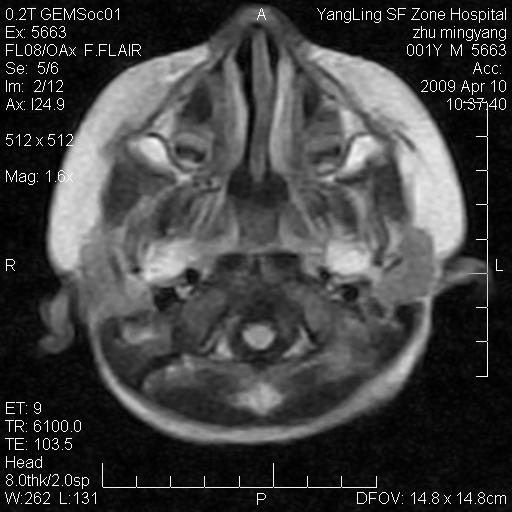

患者:1岁半,两天前外伤收住我院,ct检查小脑占位

考虑星形细胞瘤,建议增强

髓母细胞瘤或血管母细胞瘤,增强后可以鉴别;影像资料见 <。鱼博浪老师的《中枢神经系统ct与mr鉴别诊断》 小脑部肿瘤章节。

髓母细胞瘤或血管母细胞瘤!支持!

支持考虑髓母细胞瘤

考虑----髓母细胞瘤可能性大

考虑髓母细胞瘤或室管膜瘤。

支持髓母细胞瘤。

考虑髓母细胞瘤。

考虑髓母细胞瘤或星形细胞瘤

考虑髓母细胞瘤.

考虑髓母细胞瘤可能性大。

小脑肿瘤.考虑髓母细胞瘤可能.

就病灶部位及临床资料首先考虑髓母.